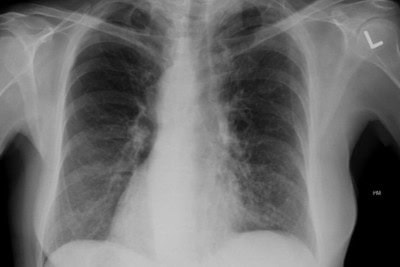

Urgent Message: This retrospective cross-sectional study found more than one-third of patients who presented to urgent care with rib injuries had rib fractures. Rib fracture was associated with male sex, older age, Spanish-speaking status, White race, and abnormal vital signs. Rebeka Sultana, MBBS; Kristin Breslin, MPH; Abigail Steiner, MS, MPH; Douglas B. Richardson, MAS; Lindsey E. Fish, MD Keywords: rib fracture; urgent care; chest wall trauma; pneumothorax; hemothorax; health disparities; logistic regression Research Supplemental Abstract …